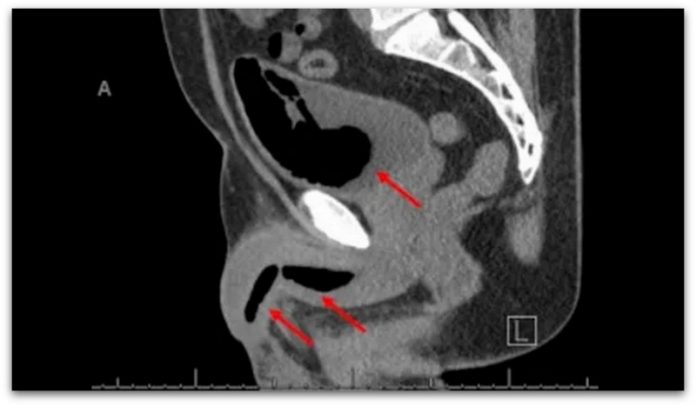

Скенирањето откри различни маси на стврдната пена, од кои некои беа долги скоро 11 см.

Медицинскиот персонал успеал да ја извади зацврстената пена од мочниот меур на мажот за време на операцијата, но масите пронајдени во пенисот се покажаа попроблематични.

Со помош на специјализирани алатки, лекарите се обиделе да ја исцицаат пената и да ја извлечат низ отворот на пенисот , но тоа се покажало невозможно.

Станало очигледно дека мажот боледувал од стриктура на уретрата – состојба во која уретрата, цевката што ја носи урината надвор од пенисот, станува полна со лузни, поради што се стеснува.

Ова ткиво со лузни ефикасно ја закотвила пената, што го оневозможува нејзиното извлекување.

Лекарите биле принудени да направат перинеална уретростомија – направиле нов отвор помеѓу скротумот и анусот, за да ги отстранат преостанатите фрагменти.